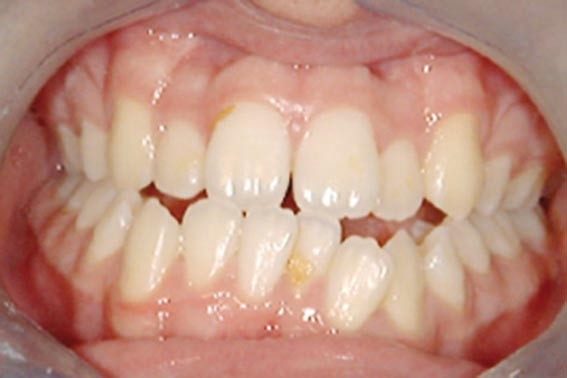

Olivier se présente à l’âge de 12 ans avec une classe III squelettique à prédominance mandibulaire, accompagnée d’une hyperdivergence et d’une endomaxillie responsable des inclusions des canines supérieures à forte obliquité. Une phase d’expansion est réalisée afin de permettre une augmentation du périmètre de l’arcade et la verticalisation des germes des canines. L’expansion permet en effet une normalisation transversale mais ne permet pas de réaliser la mise en place des canines. Les extractions des prémolaires sont alors effectuées et une préparation primaire de l’arcade supérieure par multi-attaches avec désinclusions et tractions des canines est réalisée.

Une pause thérapeutique est ensuite entamée jusqu’à la fin de croissance soit 18 ans. Une poursuite du traitement par préparation secondaire à la chirurgie orthognathique bimaxillaire est programmée.